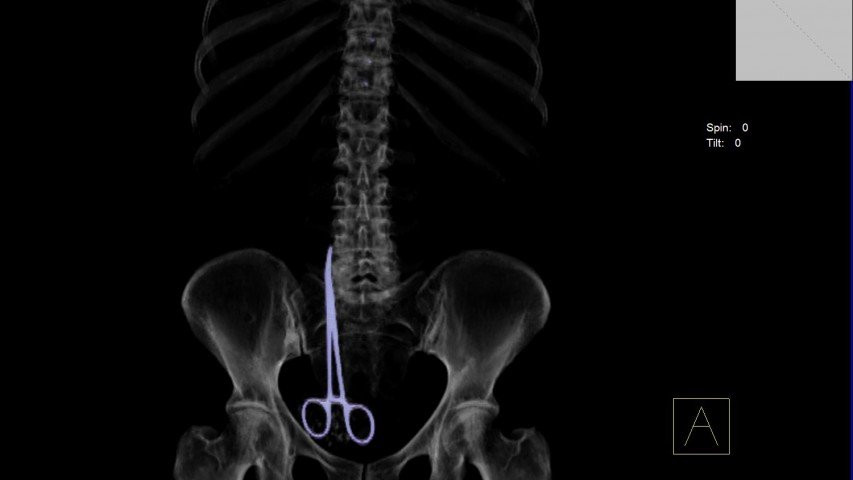

Cây kéo phẫu thuật dài 16 cm trong cơ thể bà Vera Petrova.

Sự việc chỉ rõ ràng, khi các bác sĩ thực hiện chụp cắt lớp vi tính cho bà Vera. Cả bà và bác sĩ đều kinh hoàng phát hiện một cây kéo phẫu thuật dài 16 cm bên trong cơ thể.